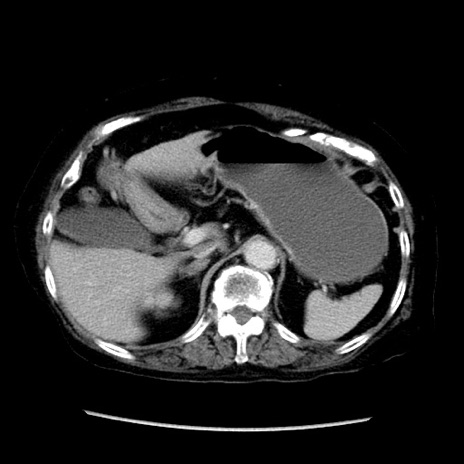

冠状断像

【症例】 90歳代女性

【主訴】 腹痛・嘔吐

【現病歴】今朝から左側腹部痛を認めた。 経過観察していたが、嘔吐を認めたため来院。

【既往歴】 子宮癌術後

【身体所見】 意識清明、BP 127/54mmHg、P 98bpm Sp02 95%(RA)、BT 35.8°C、腹部平坦・軟腸ぜん動音聴取良好、右下腹部圧痛(+) 反跳痛なし

【データ】WBC 9800、CRP 0.46